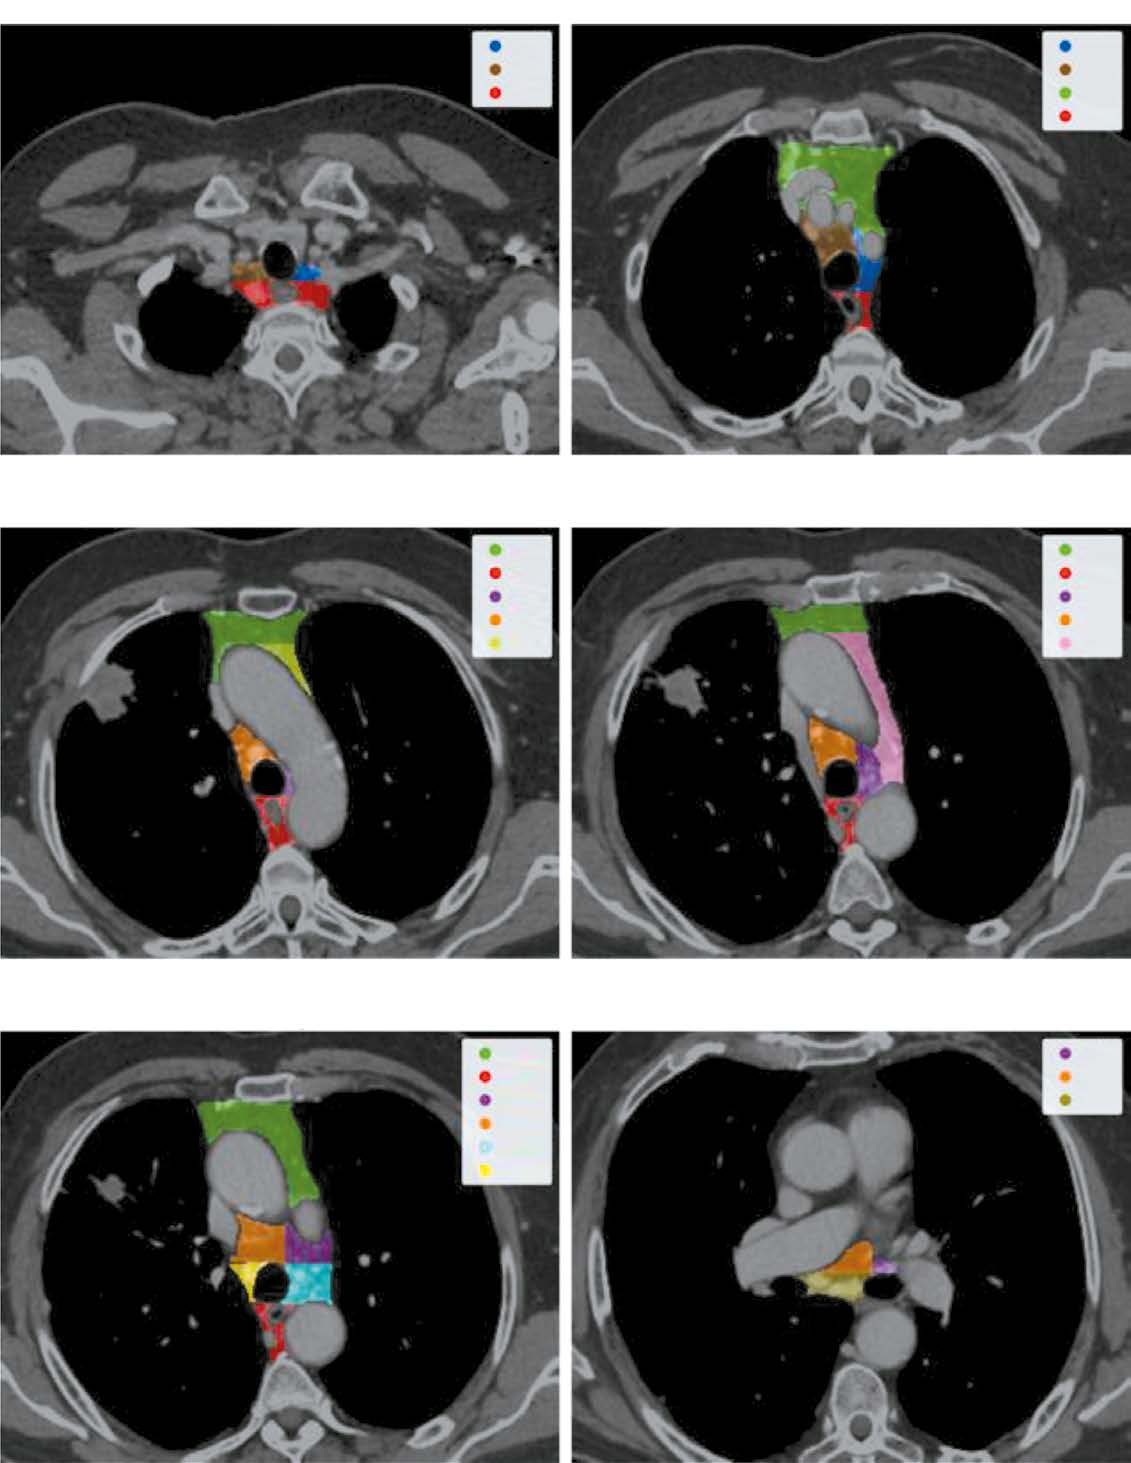

材料与方法。数据分割与处理:按照国际肺癌研究协会建议,对 淋巴结组 进行分割;获取纵隔区域的限制性矩形框,用于后续数据处理。深度学习技术应用:使用第一个神经网络对图像裁剪;使用第二个神经网络识别所有可视淋巴结并生成掩膜;在最后阶段,分离每个可视淋巴结,应用掩膜并利用前馈网络评估其转移的可能性。